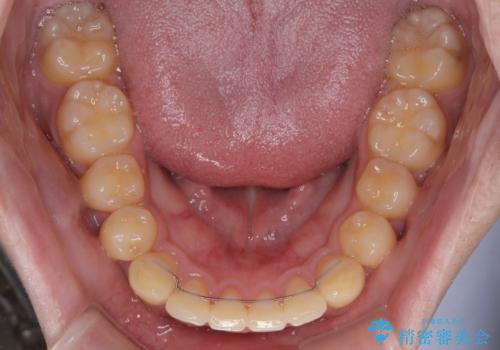

- 矯正装置

- 審美装置

昼休みを活用して通院してくださり、1年半であっという間に終えることができました。